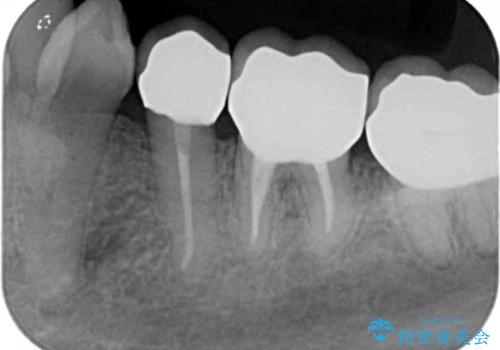

- 虫歯治療、老朽化した銀歯や詰め物 コンポジットレジンのやりかえを希望され来院されました。

クラウンやレジン下に再発していた虫歯を丁寧に除去したのち、歯ぐきの腫れが改善が見られないため歯周外科を行い歯ぐきの状態を整えたのちにジルコニアクラウンを製作していきます。